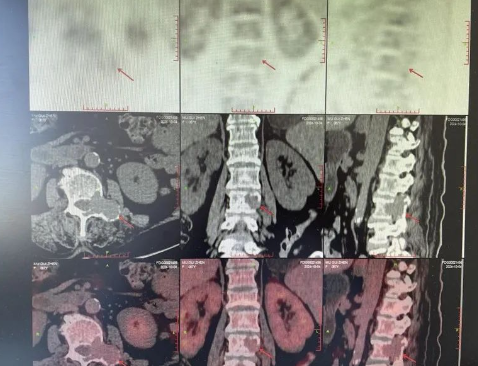

雖然醫(yī)生一直安慰,但劉阿姨平靜的生活被擊得粉碎,本是與老伴安享晚年的時(shí)候,現(xiàn)卻臥床不起,劉阿姨心中有著說(shuō)不出的酸楚。CT影像上,骨骼像被蟲(chóng)蛀了一般的空洞清晰可見(jiàn),這些空洞無(wú)聲地訴說(shuō)著疾病的殘酷。